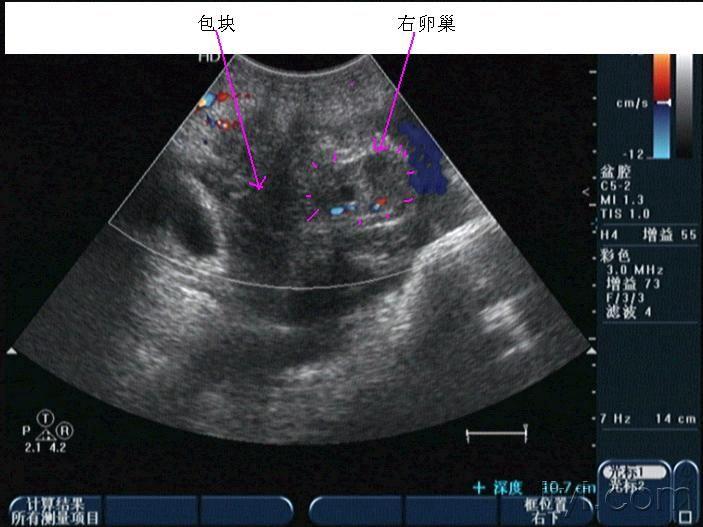

早孕并黄体破裂

晚上房事后腹痛入院,第二天早晨8点多超声所见如下,手术证术为黄体破裂。